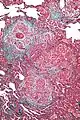

High magnification micrograph of hypersensitivity pneumonitis showing granulomatous inflammation. Trichrome stain.

The acute form can be characterized by poorly formed noncaseating interstitial granulomas and mononuclear cell infiltration in a peribronchial distribution with prominent giant cells.[1] The subacute, or intermittent, form produces more well-formed noncaseating granulomas, bronchiolitis with or without organizing pneumonia, and interstitial fibrosis.[1] Much like the pathogenesis of idiopathic pulmonary fibrosis (IPF), chronic HP is related to increased expression of Fas antigen and Fas ligand, leading to increased epithelial apoptosis activation in the alveoli.[21] Cholesterol clefts or asteroid bodies are present within or outside granulomas.[1]